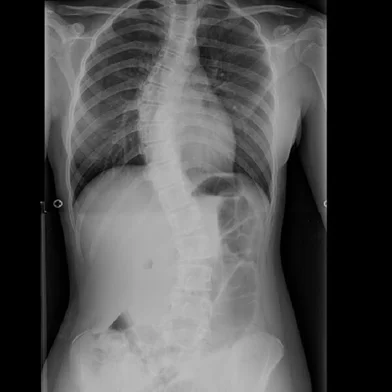

Como o verão pode ajudar a revelar alterações na coluna

Roupas leves facilitam o diagnóstico da escoliose. Observação possibilita o diagnóstico e ajuda a prevenir cirurgias